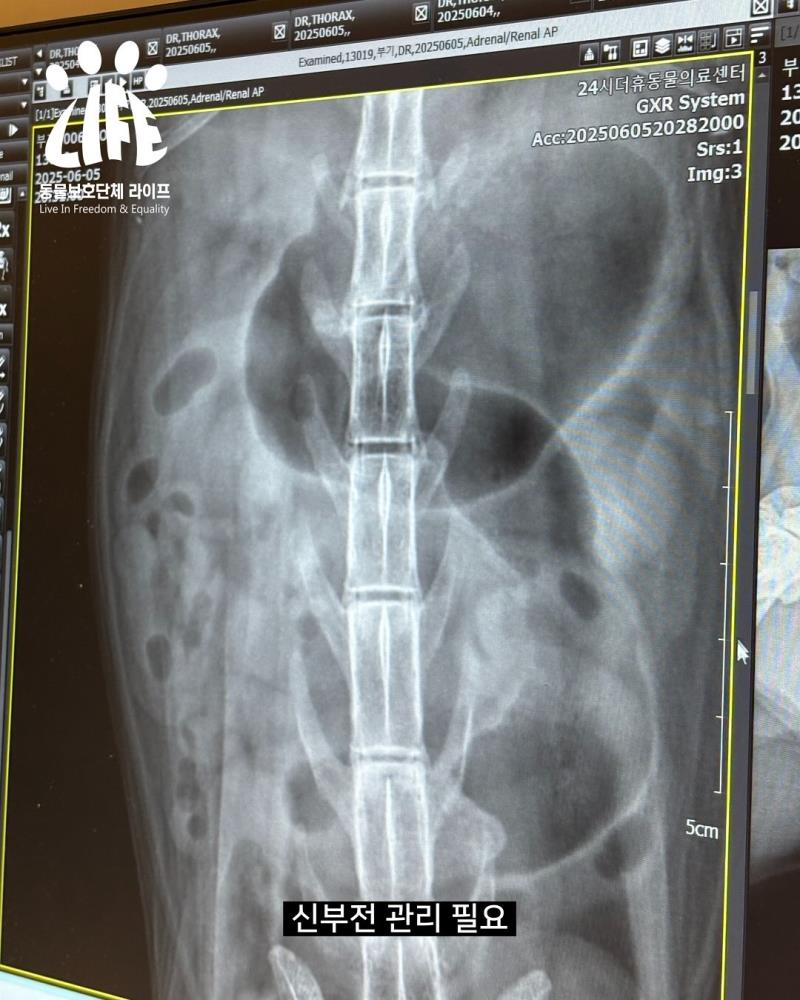

아이에게 ’꼬부기‘라는 이름을 붙여주고, 병원 진료에 들어갔습니다. ’부기‘는 8~9살 추정의 남자 아이로 중성화가 되어있었고 다른 특이점은 없었으나 신부전이 확인되었습니다.

당장의 피하수액 처치 등이 필요한 정도는 아니여서 여러 환경 변화로 힘들 아이에게 무리하지 않기로 하고 식이 관리를 하기로 결정했습니다.